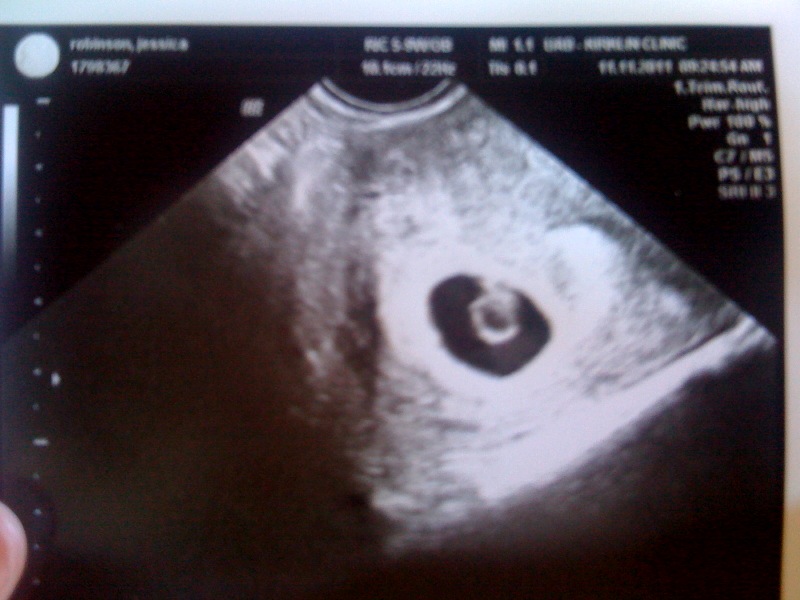

Here are some pictures of recent to sum up my wonderful days with the kiddos. Love you two!